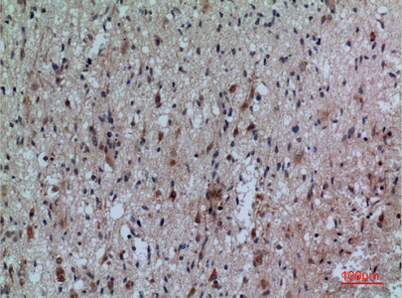

Product name: CD307 rabbit pAb

Dilutions: Western Blot: 1/500 - 1/2000. IHC-p: 1:100-300 ELISA: 1/20000. Not yet tested in other applications.

Immunogen: The antiserum was produced against synthesized peptide derived from the Internal region of human FCRL5. AA range:191-240